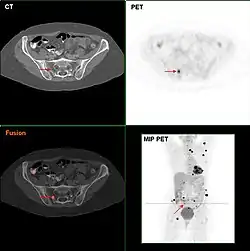

Befundung

Die Befundung des PET- oder PET/CT-Bildes erfolgt durch Betrachtung der rekonstruierten Schnittbilder (axial, koronar oder sagittal). Bei PET/CT-Geräten ist die Darstellung von PET und CT verknüpft, so dass automatisch die Position des korrelierenden PET-Bildes gezeigt wird, wenn der Bildkursor im CT-Bild verschoben wird.

Für eine Übersichtsdarstellung wird ein sogenanntes MIP-Bild (Maximum Intensity Projection) herangezogen. In dieser Darstellung ist das gesamte Untersuchungsobjekt abgebildet und man erlangt einen schnellen Überblick über Regionen erhöhter Aufnahme. Zur nochmals besseren Visualisierung kann man das MIP um sich selbst rotieren lassen, um das Untersuchungsobjekt von allen Seiten zu zeigen.

Darmkrebs

Die Detektierbarkeit von Tumoren und Metastasen des Darmkrebs wird durch den Umstand beeinträchtigt, dass sich FDG durch physiologische Prozesse ohnehin im Darm anreichert, was das Signal-Rausch-Verhältnis verschlechtert. Hier hat die PET/CT eine signifikant bessere Diagnostik im Vergleich zur reinen PET gebracht, da sie die anatomische Zuordbarkeit von Anreicherungen stark verbessert hat.

Metastudien haben gezeigt, dass die PET/CT in Bezug auf Sensitivität und Spezifität der CT, der MRT und dem Ultraschall überlegen ist. Eine Studie berichtet von 94 % Sensitivität und 87 % Spezifität. Bei Patienten mit CEA-Anstieg, bei denen die Computertomographie keine Tumorlokalisation ermöglichte, zeigte die PET eine Sensitivität von über 80 %. Eine klare Stärke der PET liegt in der frühen Diagnostik des Ansprechens einer Chemotherapie, wo sie „Responder“ (Tumor spricht auf die Chemotherapie an) und „Non-Responder“ sehr früh zu klassifizieren vermag.[30]